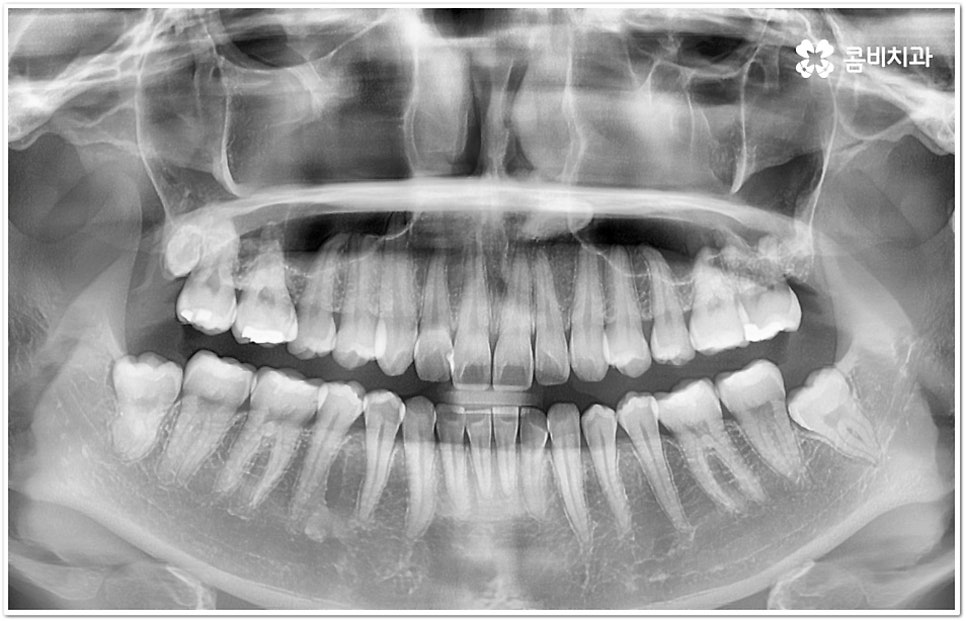

현재는 크게 불편함이 없고 환자분들의 입장에서 볼 때 스스로 교정이 딱히 필요하다고 생각되지 않는다고 해도 정밀 검진을 받아보는 것이 도움이 되는 또 다른 이유는 덧니가 생긴 원인, 구조적인 부분 등을 꼼꼼하게 체크해 봤을 때 혹시라도 추후에 치열이 더 많이 삐뚤어지거나 턱관절에 좋지 않은 영향을 줄 수 있는 상황이라면 미리 대처할 수 있다는 데 있어요. 본을 떠 보고 3D CT 를 이용해 겉으로 보이지 않는 부분까지 함께 살펴보면서 악궁 및 치아의 크기와 각도, 상악과 하악의 발달 정도 등 각자의 상황을 종합적으로 분석해 보면 앞으로의 이동 방향이나 정도 등을 어느 정도 예측해 볼 수 있는데요. 가능하다면 문제가 커진 다음에 바로잡는 것보다 지속적인 관찰을 통해 적절한 시기에 필요한 치료를 하는 것이 시간과 노력을 덜 들이는 방법이 될 거예요.

덧니의 원인에는 여러 가지가 있는데 대표적으로는 유치가 너무 일찍 빠져서 영구치가 제대로 자리를 잡지 못했거나 턱뼈의 크기와 치아 크기가 조화를 이루지 못하는 경우 등 공간이 부족한 상황을 생각해 볼 수 있어요. 덧니는 주로 송곳니가 가장 흔하나, 치열이 공간이 부족할 경우 이론적으로는 어떤 치아라도 덧니가 될 수 있어요. 이때 원인과 정도를 꼼꼼하게 파악하여 만약 해당 부위만 부분 교정이 가능하다면 덧니부분교정 치료를 할 수 있는데요. 덧니부분교정 을 이용하면 원하는 부위에만 브라켓을 부착하여 치아 이동을 시키기 때문에 전체 교정에 비해서 간편하며 치료 기간도 6~8개월 정도로 줄어들고 통증도 많이 감소될 수 있습니다. 비용적인 부담도 덜하며 (삐뚤어진 정도나 상태에 따라 다르겠지만) 보통 덧니부분교정 의 경우 비발치 과정으로 진행되기 때문에 환자분들의 입장에서는 덧니부분교정 을 많이 선호하시는 편이라고 할 수 있어요. 상황에 따라 미니스크류, 치간삭제, 악궁확장장치 등 환자에게 맞는 비발치 방법을 이용하여 도움 받을 수 있습니다.

하지만 모두에게 덧니부분교정 을 적용할 수 있는 것은 아니므로 먼저 3D CT와 같은 정밀 검사 장비를 통해서 턱의 구조적 특성 및 치열과 교합 등 구강 내부 상황에 대해 세세하게 검진을 하고 충분한 상담을 통해 각자에게 적합한 계획을 세운 다음 무리하지 않게 치료를 진행할 필요가 있어요. 만약 부분 교정을 진행할 수 없다고 해도 교정 장치를 이용하여 기간이나 통증 부분의 부담을 덜 수 있으니 너무 실망하실 필요는 없을 거예요.